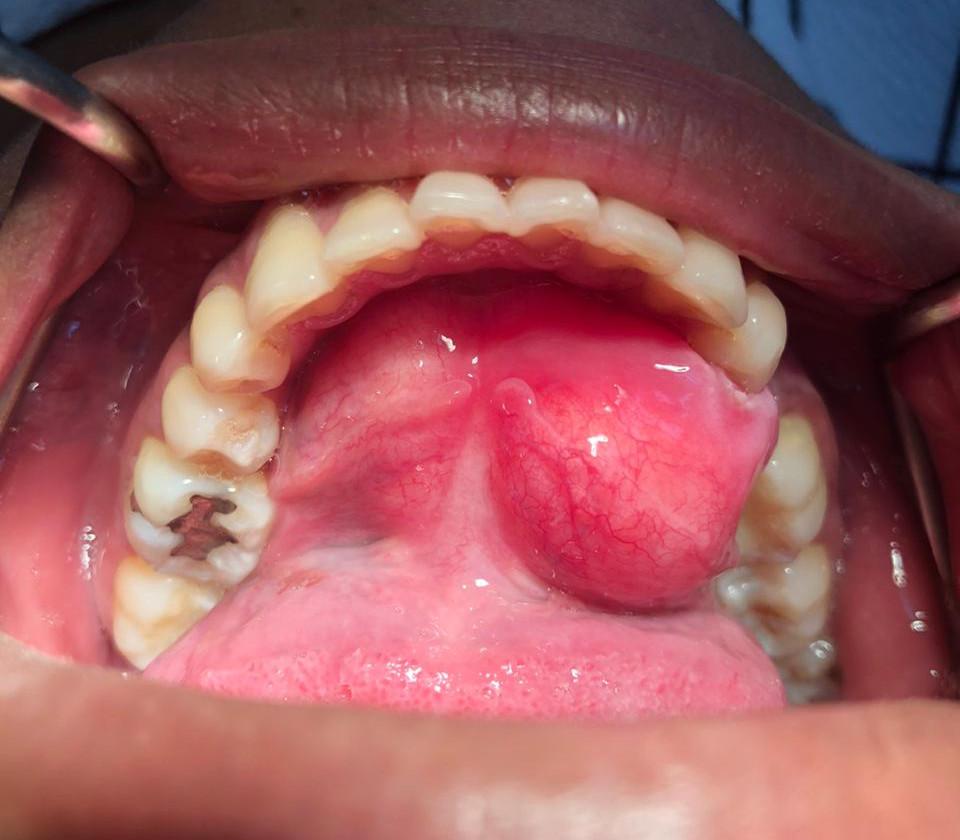

Cirugía de lipoma Bucal

antes Cirugía de lipoma Bucal despues Cirugía de lipoma Bucal

Se realizó una cirugía explorativa con anestesia local para extraer tumor y enviarlo a realizar bioxia.